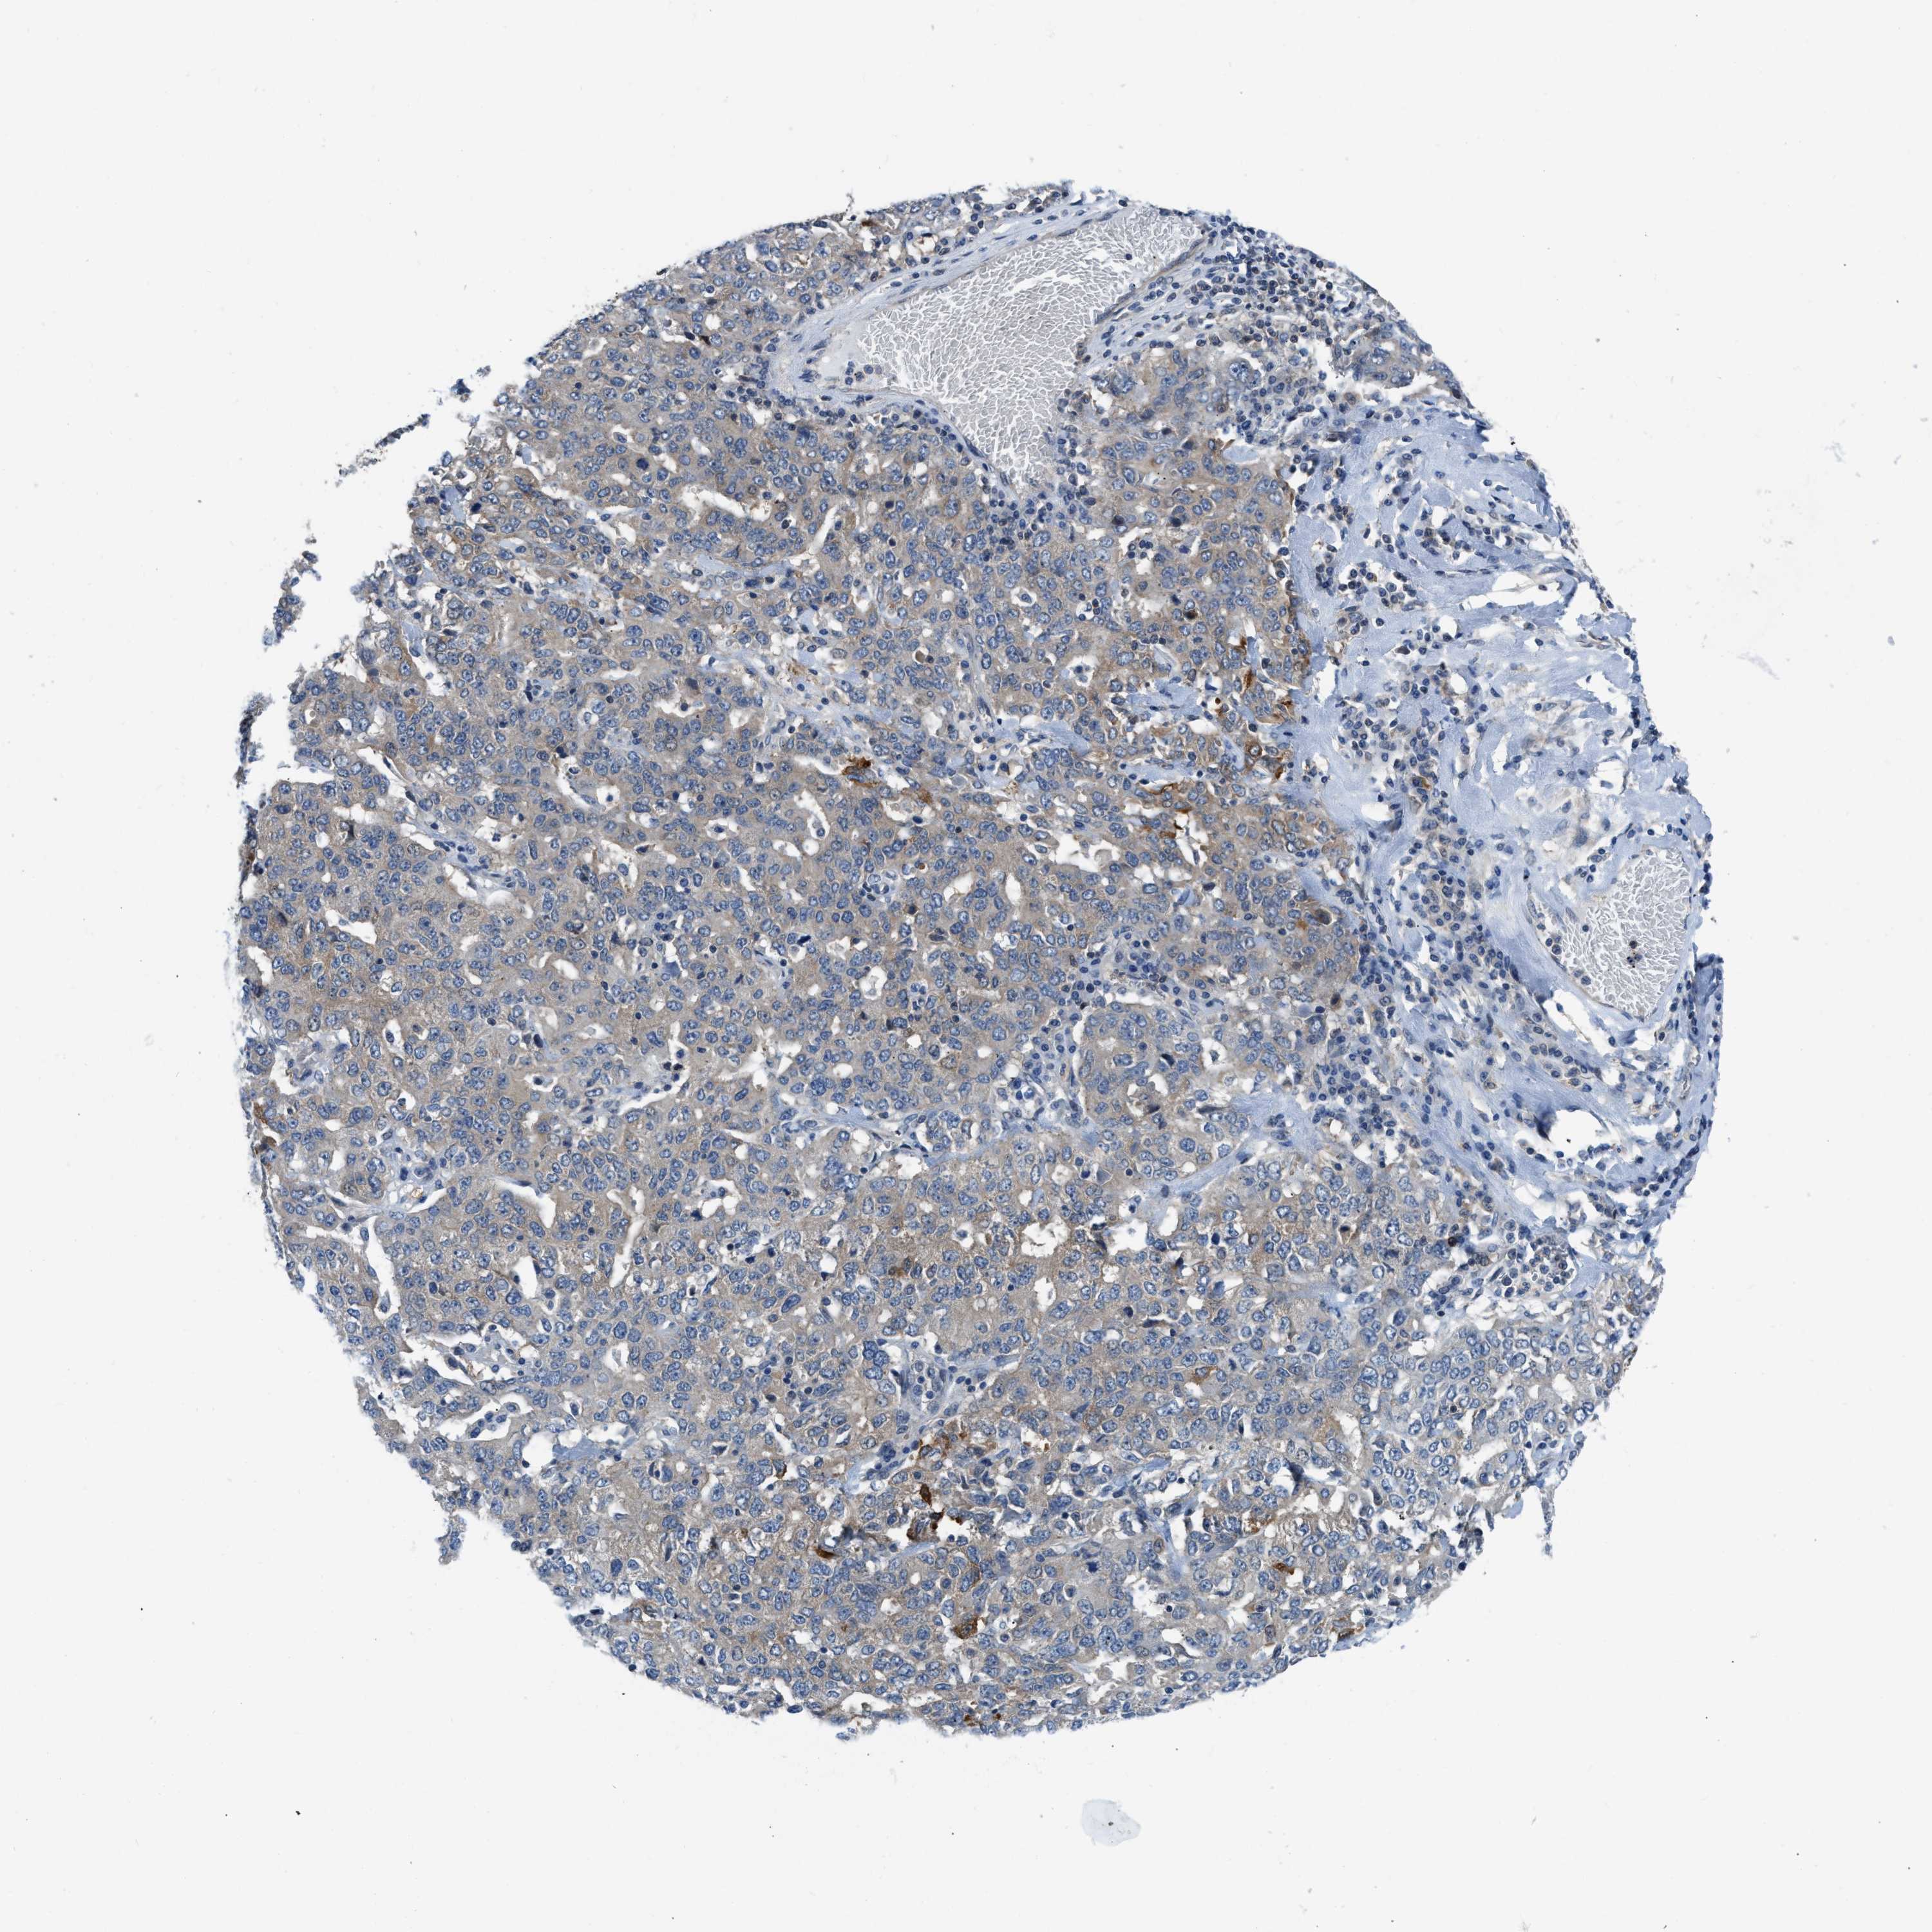

OVARIAN CANCER - Protein expressioni

A mouse-over function shows sample information and annotation data. Click on an image to view it in a full screen mode. Samples can be filtered based on level of antibody staining by selecting one or several of the following categories: high, medium, low and not detected. The assay and annotation is described here.

Note that samples used for immunohistochemistry by the Human Protein Atlas do not correspond to samples in the TCGA dataset.

Antibody stainingi

Antibody staining in the annotated cell types in the current human tissue is reported as not detected, low, medium, or high, based on conventional immunohistochemistry profiling in selected tissues. This score is based on the combination of the staining intensity and fraction of stained cells.

Each image is clickable and will lead to virtual microscopy that enables deeper exploration of all samples and also displays staining intensity scores, fraction scores and subcellular localization as well as patient and tissue information for each sample.

Antibody HPA018257

Staining

High

Medium

Low

Not detected

Intensity

Strong

Moderate

Weak

Negative

Quantity

>75%

75%-25%

<25%

None

Location

Nuclear

Cytoplasmic/membranous

Cytoplasmic/membranous,nuclear

Cystadenocarcinoma, serous, NOS

Carcinoma, endometroid

Cystadenocarcinoma, mucinous, NOS

Carcinoma, NOS